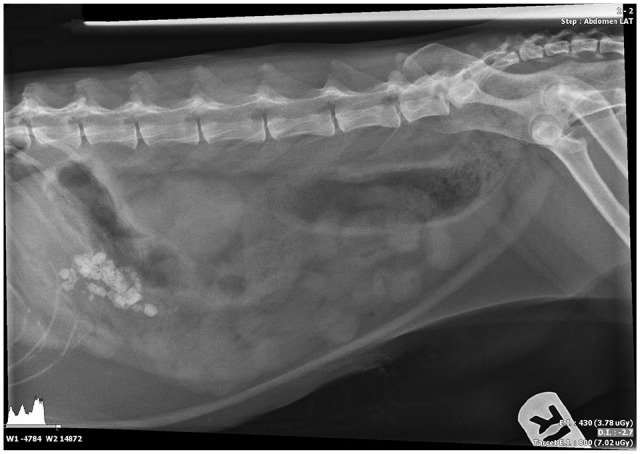

Case summary: A 7-year-old castrated male domestic shorthair cat was presented for surgical intervention for obstructive pancreatolithiasis. The patient had a history of chronic weight loss, vomiting and lethargy. Elevation of feline pancreas-specific lipase and a marked decrease in cobalamin were documented on blood biochemistry. Abdominal ultrasound revealed an enlarged right pancreatic limb with a dilated central duct and multiple pancreatoliths visualized within, consistent with partial pancreatic duct obstruction. The patient was successfully treated with a minor duodenal papilla construction using a 2.5 Fr double pigtail ureteral stent.

Relevance and novel information: Pancreatolithiasis is an exceptionally rare condition in veterinary medicine, particularly in cats, with only a few reported cases. Given its low incidence, there is no established consensus regarding the best therapeutic options in clinical practice. This case report outlines the successful application of a locking loop catheter to re-establish the patency of a pancreatic duct. Notably, this is the first documented use of this technique for the surgical management of obstructive pancreatolithiasis.